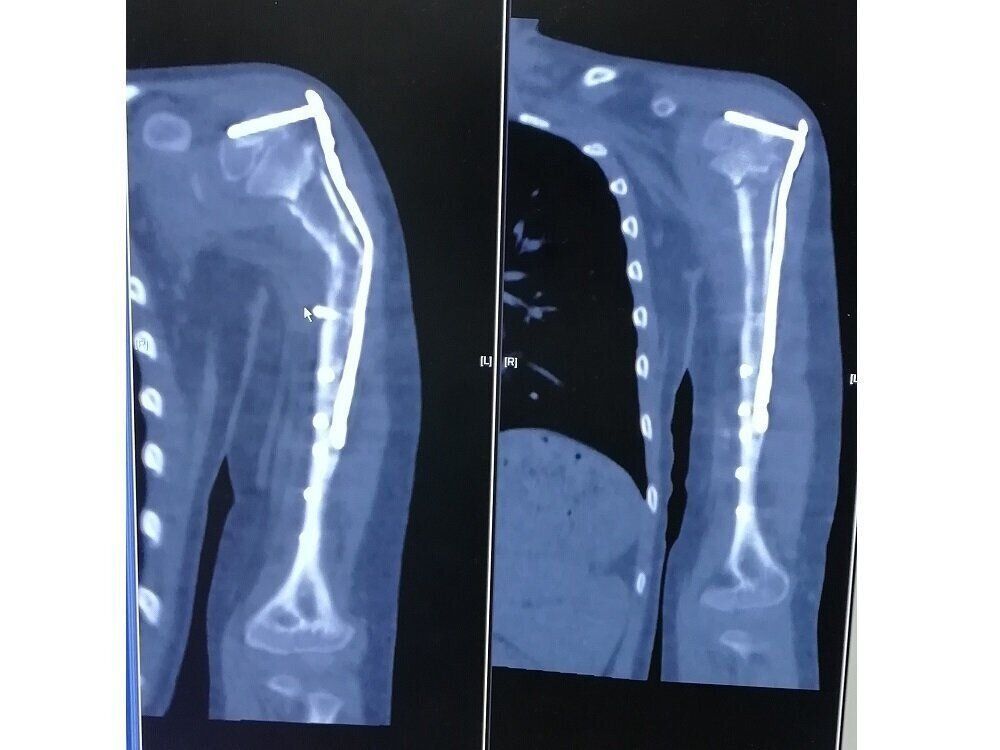

手術は、腫瘍ができた骨をまわりの筋肉などで包んでいったん切除して、腫瘍を取り除いたあとに骨を液体窒素につけてから、体に戻すというものでした。液体窒素につけるのは腫瘍細胞を死滅する効果が期待できるからなのだそうで、液体窒素につける時間は20分程度なのだとか。病気のある骨を再利用する方法で、日本を中心に発展してきた技術だと聞きました。

半年たっても骨折が治らないため、2020年のひな祭りの日に、足のすねの骨を腕に移植することになりました。

手術後、すみれの腕はギプスでがっちり固められていました。腕だけではなく、足も不自由なことになってしまうのかと落ち込みました。でも、足の動作にあまりかかわっていない骨なんだそうで、手術後も普通に歩いている姿を見て、ホッと胸をなでおろしました。

しばらくの間ギプスや三角巾生活を続けたのち、足の骨が腕に固定したことが確認され、腕に差し込まれたボトルを抜く手術を1年後に行いました」(すみ子さん)

骨の腫瘍を切除したあとの治療として、病気を含んだ骨を液体窒素で凍らせて、がん細胞を死滅させたうえで、同じ場所に戻す方法があります。これは自分の骨を再利用できる治療法で、日本を中心に行われており、広く使われています。

がん細胞をなくす方法には、ほかにも放射線を当てたり、高温で消毒したりする方法(パスツール処理)もあります。海外では、ほかの人の骨を使う移植が多く使われています。また、すみれさんの2回目の手術のように、自分の足の骨を使う方法もありますが、自分の骨をそのまま使えるこの方法は、体のほかの部分を傷つけずにすむのが特徴です。

手術後は、腕がしっかり動いているか、左右の長さに差が出ていないかを診察していきます。また、再発がないかを確認するために、定期的にCTやMRIなどの検査を行いながら慎重に見守っていきます。